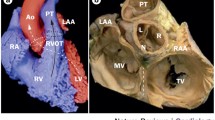

The OT are structures located at the base of the heart [9] (Video 1). The proximal RVOT begins at the superior margin of the tricuspid annulus and lies to the right of the LVOT here. As the RVOT extends superiorly, the mid and distal RVOT wrap around the LVOT and therefore contrary to its name the RVOT is located anteriorly and more leftward than the LVOT. The structure therefore immediately anterior to the aortic valve is the posterior muscular infundibular portion of the RVOT (Fig. 1). The pulmonic valve is located to the left and anterior (5–10 cm) to the aortic valve. The posterior RVOT is immediately anterior to the right coronary sinus of Valsalva cusp (RCSoV) and a portion of the left coronary sinus of Valsalva (LCSoV). Therefore, the posterior RVOT has no true epicardial surface in contrast to the anterior RVOT. The LVOT is not entirely muscular (like the RVOT) and has a fibrous portion. There is no infundibulum below the aortic valve. This difference in anatomy can be attributed to the differential absorption of the subvalvular infudibulae below the aortic (AoV) and pulmonary valves (PV) [10]. Extensions of muscle sleeves are noted above the valves in both the outflow tracts (LCSoV 24%, RCSoV 54% [11], PV 74% [12]).

Reconstructed computed tomographic image showing the anatomy and interrelationship between the outflow tracts. RVOT right ventricular outflow tract; LVOT left ventricular outflow tract; RV right ventricle; LV left ventricle; PA pulmonary artery; SoV sinuses of Valsalva; CS coronary sinus; MCV middle cardiac vein; GCV great cardiac vein, RAO right anterior oblique; LAO left anterior oblique

Video 1 Reconstructed computed tomographic image showing the anatomy of the outflow tracts